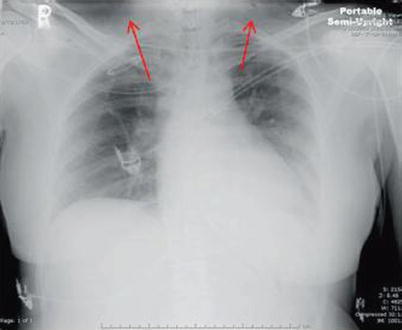

Fig. 15.1

Image of a left flail chest (red ellipse) with associated subcutaneous emphysema (red arrow)

Soft tissue emphysema is another common abnormality that is often identified on radiographic imaging (Figs. 15.1 and 15.2). The presence of soft tissue gas should alert you to look for additional intrathoracic pathology. The most common scenario is subcutaneous air with ipsilateral rib fractures. This constellation of findings should be presumed to signify a pneumothorax, even if not readily identifiable on the radiograph.